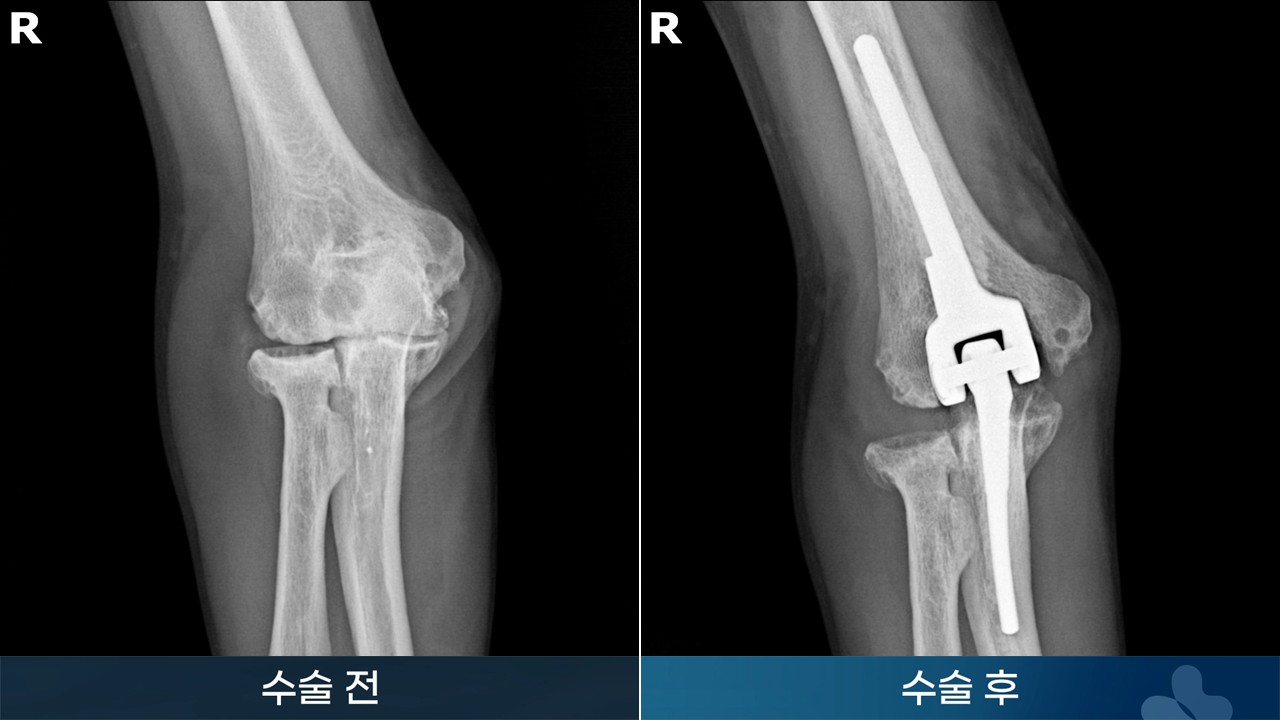

※ 수술 경과는 개인에 따라서 달라질 수 있습니다. 수술 후 멍, 감염, 통증, 부종 등이 발생할 수 있습니다.